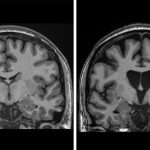

Dos escáneres cerebrales uno al lado del otro. El de la izquierda es saludable, el de la derecha muestra la pérdida de materia cerebral a medida que las neuronas mueren en la enfermedad de Huntington.